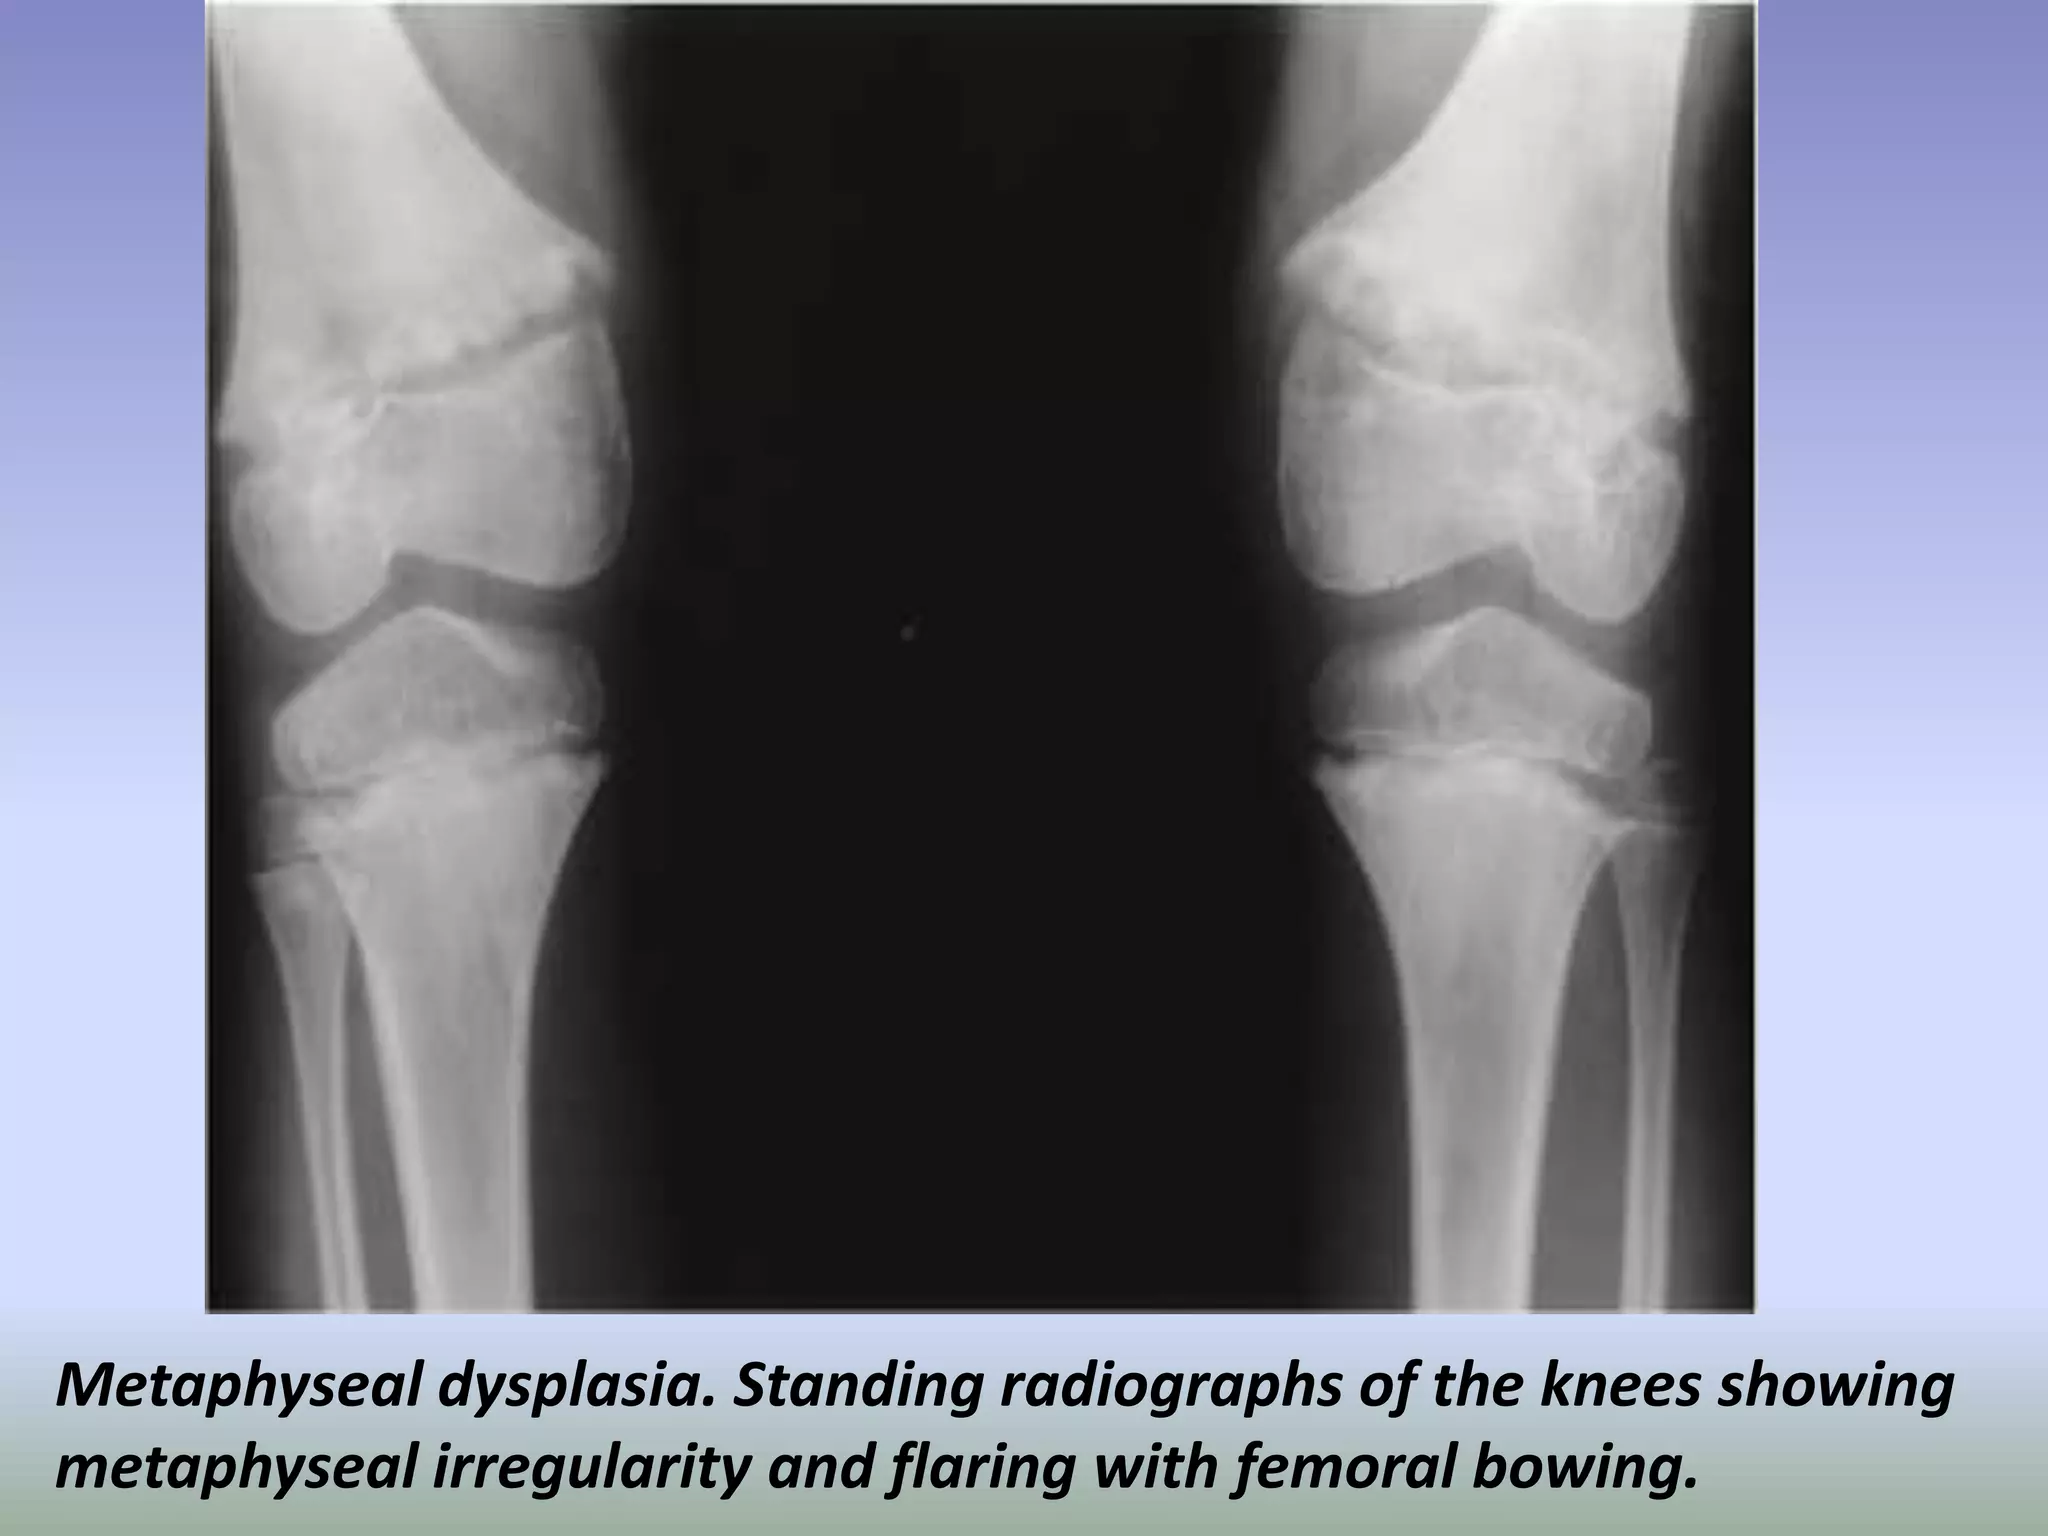

Metaphyseal dysplasia. Standing radiographs of the knees showing

metaphyseal irregularity and flaring with femoral bowing.